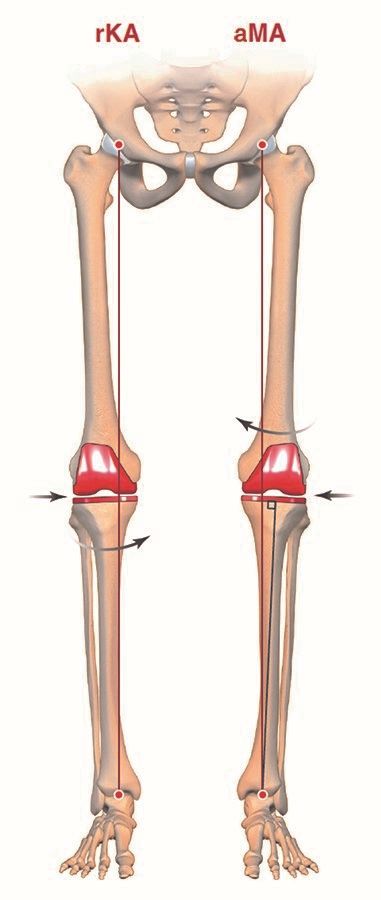

Key Points: Traditional MA utilizes systematic bone cuts perpendicular to the mechanical axis, often necessitating soft tissue releases. Anatomical alignment (AA) modifies this by targeting a 3° varus joint line while maintaining a neutral limb axis. Adjusted mechanical alignment (aMA) allows for residual constitutional varus up to 5°. Kinematic alignment (KA) aims to restore pre-arthritic joint surface orientation and laxity without soft tissue release, though concerns persist regarding long-term component fixation in cases of severe tibial varus. Restricted kinematic alignment (rKA) proposes a hybrid approach, utilizing KA principles within a defined "safe zone" (coronal alignment ≤3° and tibial obliquity ≤5°) to avoid extreme outliers.

Therefore, some authors have opted for a compromise when performing a TKA on patients with substantial limb deformity. Using computer assisted tools they assess limb frontal alignment and proximal tibial joint surface obliquity during the procedure. They then perform the arthroplasty using the KA technique if constitutional frontal limb deformity ≤ 3° and proximal tibial joint obliquity ≤ 5° obliquity (safe alignment zone) (39). Otherwise, in approximately 40% of cases, the authors adjust the bone cut (tibial and/or femoral) to bring the patient into their safe alignment zone. Otherwise the rKA technique (Figure 9) follows the same principles as the classical KA technique.